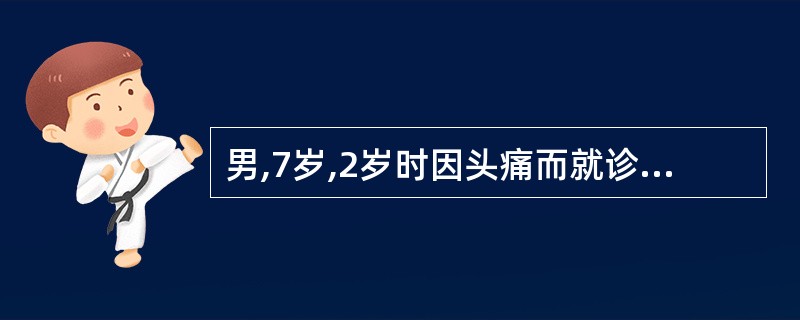

男,7岁,2岁时因头痛而就诊,MRI示脑积水、颅内(小脑蚓部及蝶鞍)见多发恶性肿瘤,临床诊断为髓母细胞瘤。未行手术治疗,多年来一直行放、化疗治疗,最后一次化疗1个月前结束。因腹胀、恶心、呕吐1周而就诊,CT示:双侧侧脑室充满肿瘤病灶,PET/CT全身显像如图。正确的描述是 ( )

A.肿瘤复发并沿双侧侧脑室弥漫性浸润

B.肿瘤同时向双侧丘脑及豆状核浸润、侵犯;蝶鞍内块状高代谢病灶,考虑为转移灶

C.脑干及颈段、胸段、上腰段脊髓内见长条状高代谢病灶,考虑为肿瘤向脑干及大部分脊髓播散、种植转移

D.正常情况下脊髓内无明显放射性浓聚,当出现椎管内肿瘤转移则可表现为 F-FDG明显浓聚,呈“辫子征”